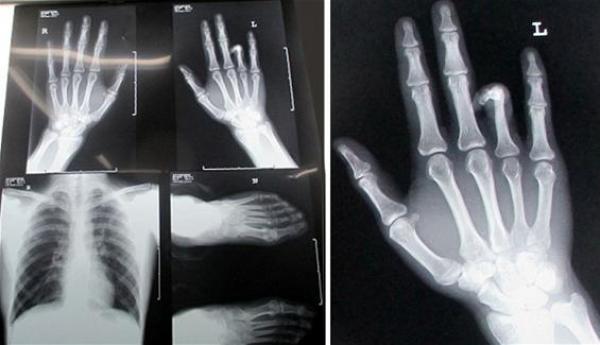

وعبر الشاب ها يوان (22 عاماً) عن سعادته البالغة بعد نجاح الجراحة، معتقداً أنه سينجح في الحصول على فرصة عمل في وظيفة بعد أن تم رفضه عدة مرات بسبب الإصبع الناقص، رغم أن نقصان الإصبع لم يكن يعيقه عن أي عمل.

ولفتت صحيفة دايلي ميل البريطانية إلى أنها ليست العملية الأولى من نوعها في الصين، إذ تمكن الأطباء قبل شهر من زراعة يد مبتورة في قدم المصاب لإنقاذها من البتر بعدما تعرض لحادث مروع في مكان عمله.